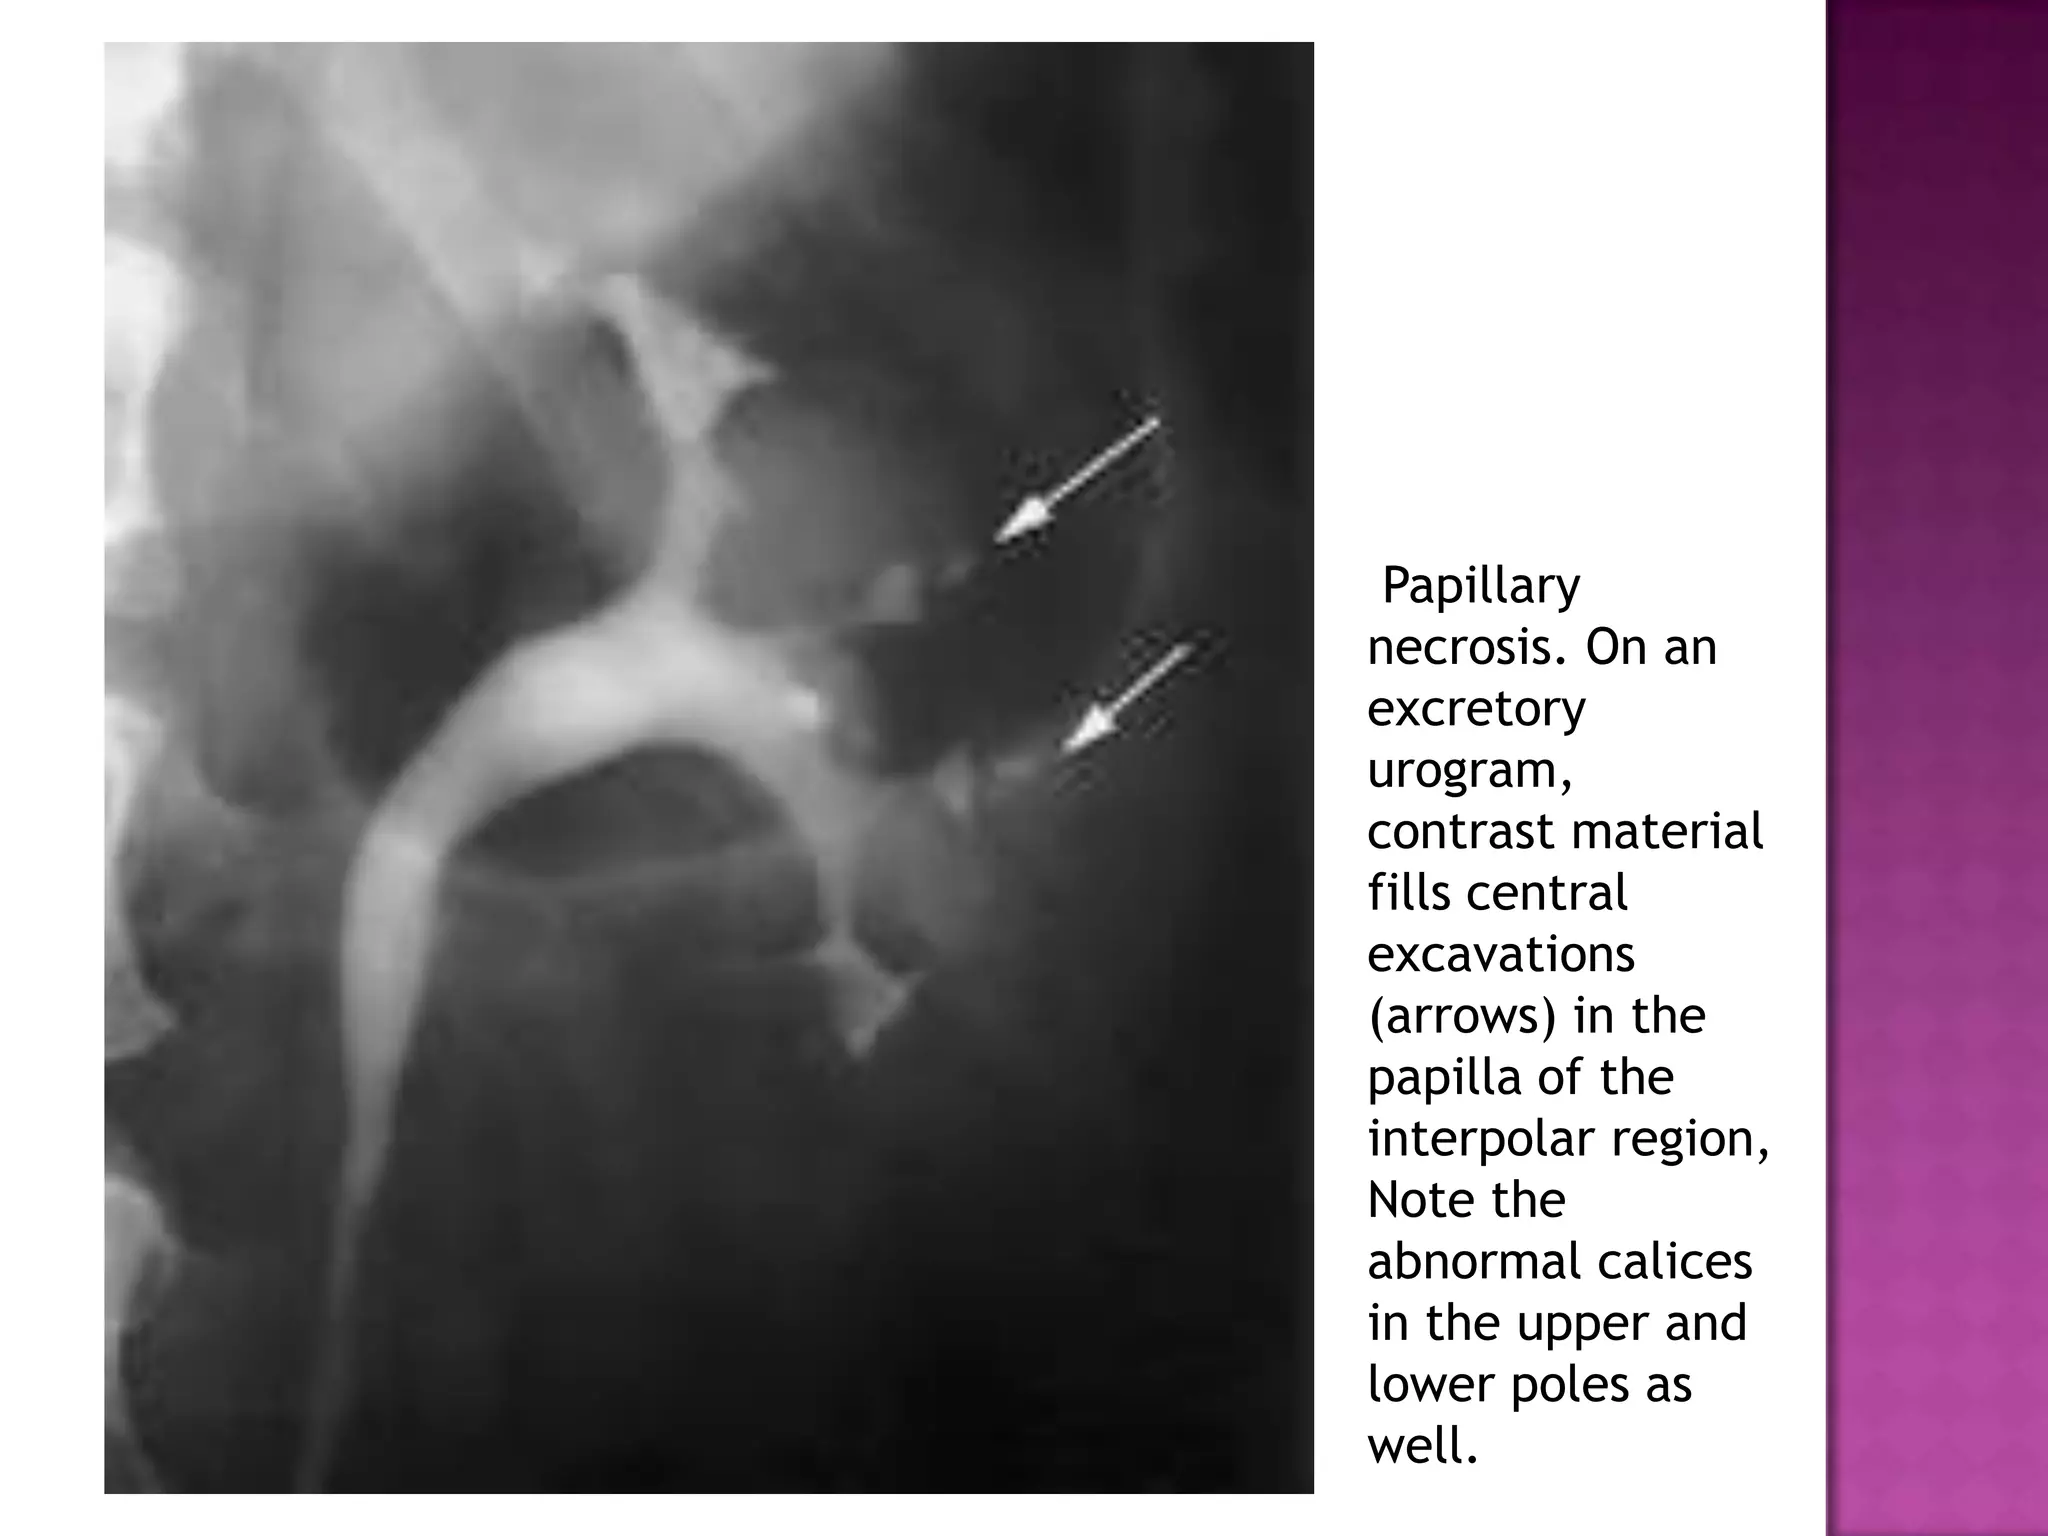

Papillary

necrosis. On an

excretory

urogram,

contrast material

fills central

excavations

(arrows) in the

papilla of the

interpolar region,

Note the

abnormal calices

in the upper and

lower poles as

well.

different patterns of excavation that can be seen with papillary necrosis:

normal (A), central excavation with ball-on-tee appearance (B), forniceal

excavation (C), lobster claw appearance (D), signet ring appearance (E), and

sloughed papilla with clubbed calix (F).

Papillary necrosis. On an excretory urogram, contrastmaterial fills central excavations (arrows) in the papilla of the interpolar region, Note the abnormal calices in the upper and lower poles as well.

different patterns ofexcavation that can be seen with papillary necrosis: normal (A), central excavation with ball-on-tee appearance (B), forniceal excavation (C), lobster claw appearance (D), signet ring appearance (E), and sloughed papilla with clubbed calix (F).